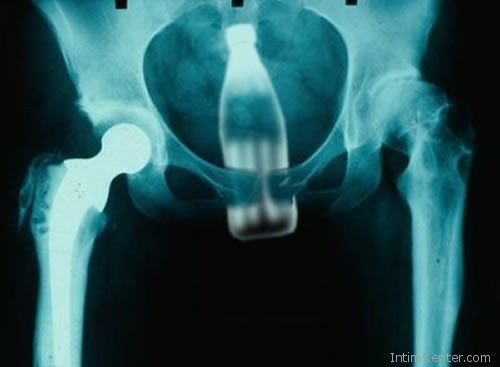

– Ami kézzel fogható, abban előbb-utóbb valaki meglátja a lehetőséget és felhasználja szexuális céljaira. Egy időben nagy sláger volt a dezodoros flakon, amit ha kupakkal felfelé dugtak be, gyakran anélkül húztak ki. Az uborka, répa, babán, fogkefe már szinte rutinmunkát ad. Arra is emlékszem, amikor egy fiatal fiú félt, hogy a kábítószeres tasakok kipukkannak a gyomrában, ezért kitalálta, hogy azokat ketchupos üvegbe rejti és alulról felhelyezi. Az akció előtt főpróbát tartott, de az üveg beszorult és a sebészeten kötött ki – meséli egy műtős.

– A gyerekkorban előforduló, az orrba feldugott és lenyelt játékdarabok említésre sem méltók. Mert amit le lehet nyelni, azt le nyelik a felnőtt emberek is. Több, mint harminc éve dolgozom az egsészségügyben, sokat láttam. – árulta el lapunknak egy nevét nem vállaló egészségügyi dolgozó, majd sorolni kezdte a „megevett” tárgyakat – A nagyobb méretű élelmiszerek általában véletlenül kerülnek a gyomorba, ide sorolnám a fogpiszkálót is. Az egy darabban lenyelt héjas burgonya, mandarin, narancs azonban már elgondolkodtató. Volt, aki lenyelte a kanalat, kést, villát és ki kellett operálni a gyomrából, de a miértre nem tudott választ adni. Láttam már fésűt, hullámcsatot, műkörmöt, tollat, zoknit és kulcsot a röntgenképeken. A rabok általában pengét szoktak lenyelni, hogy ha csak pár napra is, de kiszabaduljanak a cellájukból.